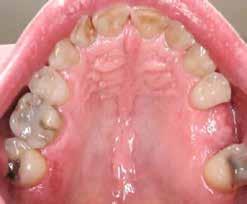

Új dimenzió a CBCT, a fogászati röntgenek és a kefalometriai felvételek diagnosztikájában a MESTERSÉGES

INTELLIGENCIA erejével csak a VIP DENTALBAN!

Dentális státusz elemzése mesterséges intelligencia által CBCT felvételen.

Panorámaröntgen elemzése mesterséges intelligencia által.

Kefalometriai elemzés és pontbejelölés mesterséges intelligencia által.

Legyen az Ön rendelője a fogászati ellátás innovatív központja, és velünk együtt biztosítsa a legmagasabb szintű diagnosztikai szolgáltatást az MI által támogatott elemzésünkkel.